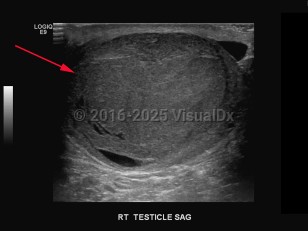

Testicular cancer

A malignant tumor of the testis (one or both), most often of germ cell origin (95%), which may be diagnosed as primary or metastatic cancer. Common presentation includes painless swelling, palpable mass or enlargement in the testis, orchidalgia, fatigue, and infertility. Other symptoms may be flank pain and dull or heavy abdominal sensation. Patients with metastatic disease, depending on the location of the metastasis, may present with gastrointestinal (GI) symptoms (nausea, vomiting, GI hemorrhage, anorexia), edema of extremities, bone pain, back pain, central nervous system abnormalities, cough, dyspnea, or neck mass. Patients with cryptorchidism have greater risk for testicular cancer.

Nonseminomatous tumors most commonly occur in patients aged 15-35, while seminomatous tumors target men a decade older. Germ cell malignancies of the testis are typically associated with a specific cytogenic irregularity (il2p). Non-germ cell tumors may arise in Leydig or Sertoli cells, or lymphomas, with non-Hodgkin lymphoma more common in men over age 60.